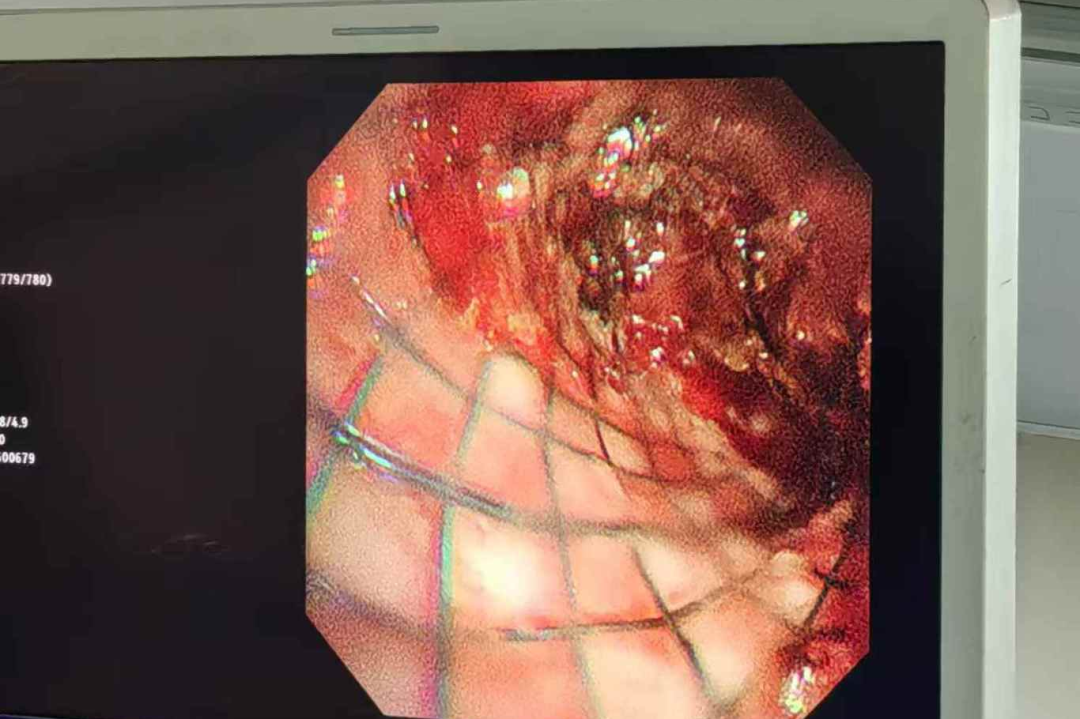

上面这位患者来自巴基斯坦,双肺多发转移病灶,经过化疗、靶向药治疗后仍有部分转移。由于病灶较大,挤压并粘连双侧支气管、左心房、双下肺静脉、胸主动脉、食管,以至于该患者气道复杂、狭窄,呼吸困难。我们介入团队在内镜联合DSA引导下,进行气道内肿瘤消融+支架植入术,反复电切、止血、消融、疏通的同时植入支架,历经近三个小时终于打通了气道,为进一步治疗争取了时间。

- 腔内消融术:通过多种物理、化学方法使肿瘤组织坏死,减少病灶组织体积。如热消融(射频、微波)、冷消融(冷冻)、光动力疗法等。

- 机械切除术:硬质镜前段直接切除、铲除、吸除或钳取肿瘤,以快速畅通气道。

其中,支架置入是指通过导管将支架送至气管内的狭窄部位,张开后起到支撑管壁,维持气道通畅的作用,从而达到改善呼吸功能的目的,主要针对恶性肿瘤引起的气管支气管狭窄进行姑息治疗,以迅速解除患者呼吸困难的症状,为后续治疗创造条件和机会。

我们介入科团队在这方面有成熟和丰富的诊疗经验。术中麻醉医生全程配合,支气管镜联合DSA在恶性气道狭窄中的活检、吸痰、止血、冷热消融及支架置入,技术成功率100%,安全且疗效满意,为患者点亮生命之光。